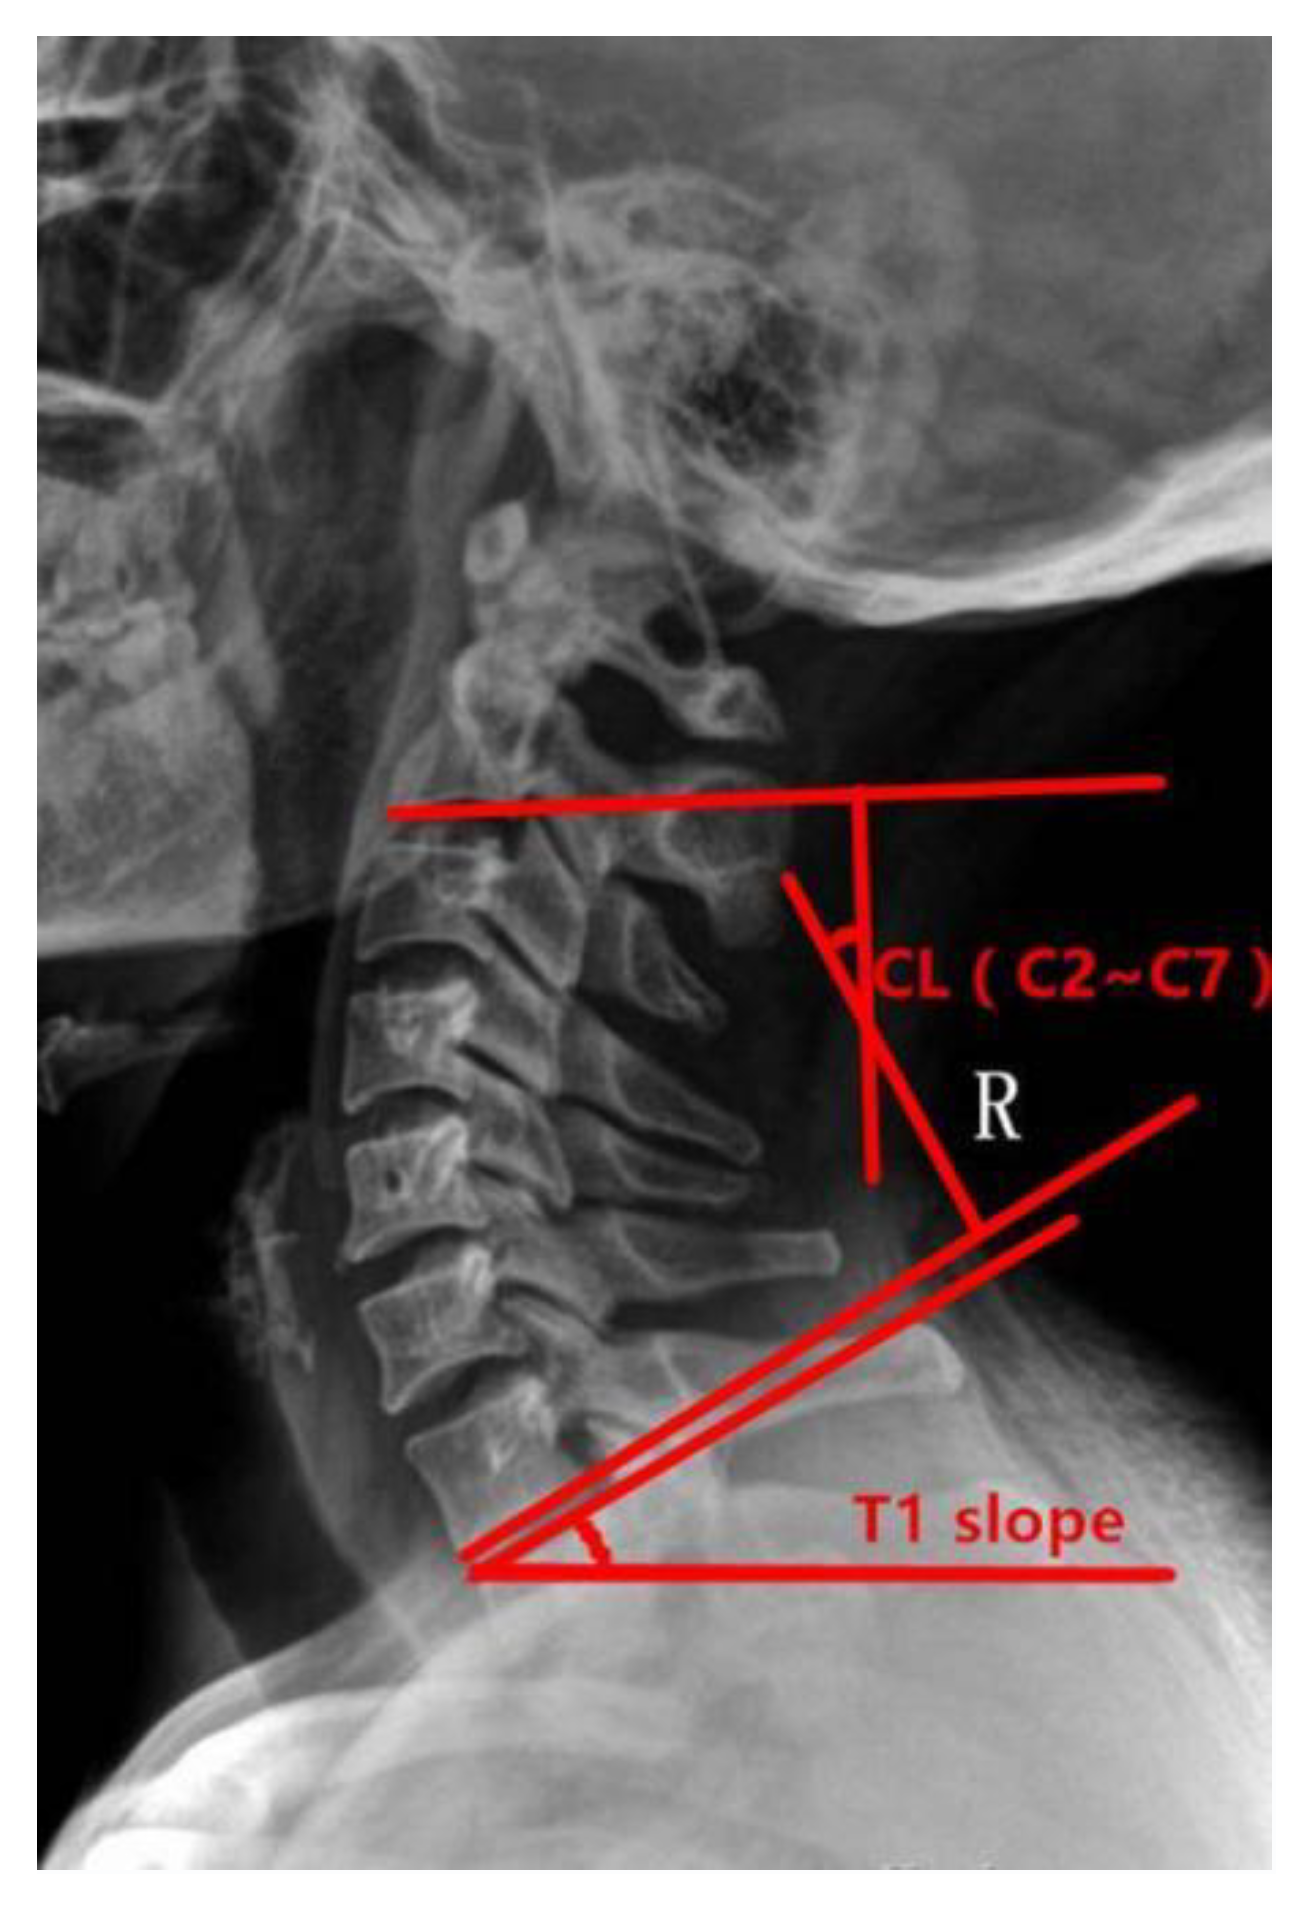

2.3. Measurement Standard